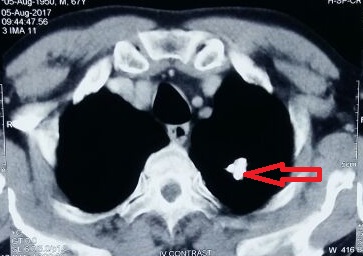

A case of Pulmonary Hamartoma

Pulmonary hamartoma, hemoptysis, fibromyxoid stromaAbstract